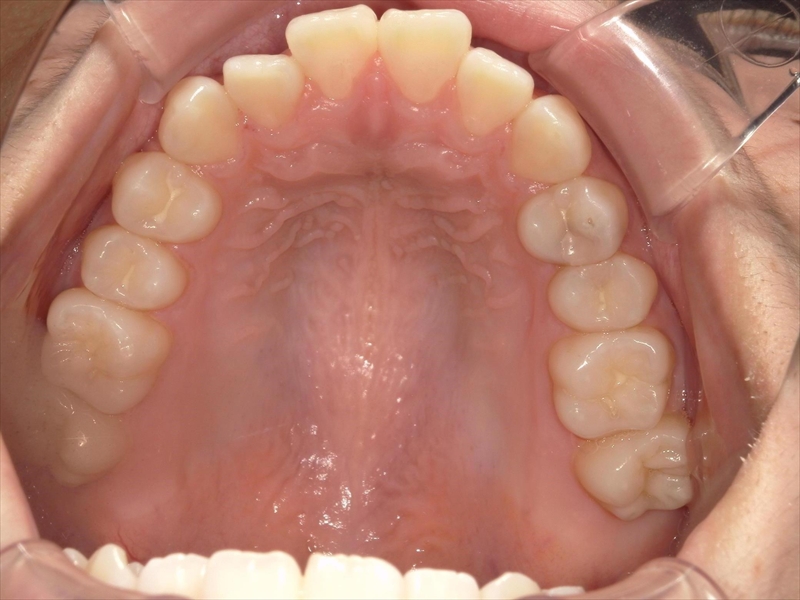

この患者様は、重度の出っ歯があり、下顎前歯には叢生が認められました。

前歯を収めるスペースを確保するために歯を削り(IPR)、奥歯から順に後方(奥)へ下げる並びを整える計画を立案いたしました。